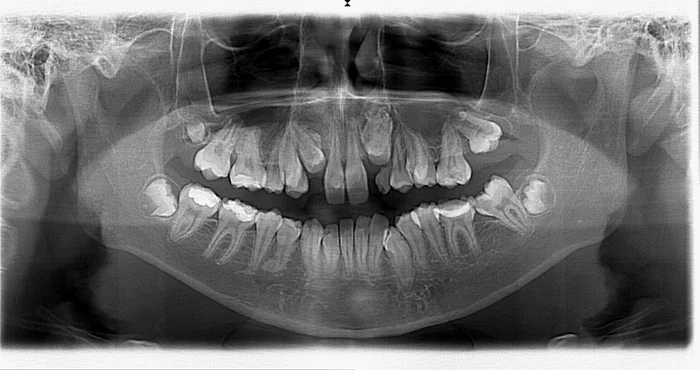

Фото: пациентка, отказавшаяся удалять зубы мудрости

Но наибольшее количество вопросов у пациентов вызывают случаи, когда необходимо удалять совершенно здоровые на их взгляд зубы мудрости, с которыми у них не было абсолютно никаких проблем, либо они еще даже не прорезались и находятся в челюсти в виде зачатков. Почему же их все-таки приходится удалять? Ответ на этот вопрос кроется в профессионализме врача ортодонта, в его способности видеть результаты лечения через год, два, десять лет. И то, что сейчас кажется замечательным, при несвоевременном лечении и непрофессиональном подходе может в дальнейшем обернуться катастрофой как для пациента, так и для доктора, и нивелировать годы упорного и, на первый взгляд, успешного ортодонтического лечения. Дело в том, что прорезывание зубов мудрости, в случаях недостатка места для них в зубном ряду, вызывает смещение других зубов. Страдают, как правило, передние однокорневые зубы. Они могут выдвигаться в сторону щеки или языка, поворачиваться вдоль своей оси, да и просто болеть. Самое обидное, когда это происходит через год-два после снятия брекет-системы. В таких случаях годы лечения прошли впустую, нужно удалять зубы мудрости и все начинать сначала. С такими пациентами наиболее сложно, так как у них пострадали не только зубы, но и доверие к врачу. Чтобы этого избежать грамотный ортодонт всегда начнет с планирования ортодонтического лечения. И в этом планировании очень часто идет хирургическая подготовка, которая включает в себя удаление зубов мудрости, прорезавшихся или находящихся на стадии зачатков.